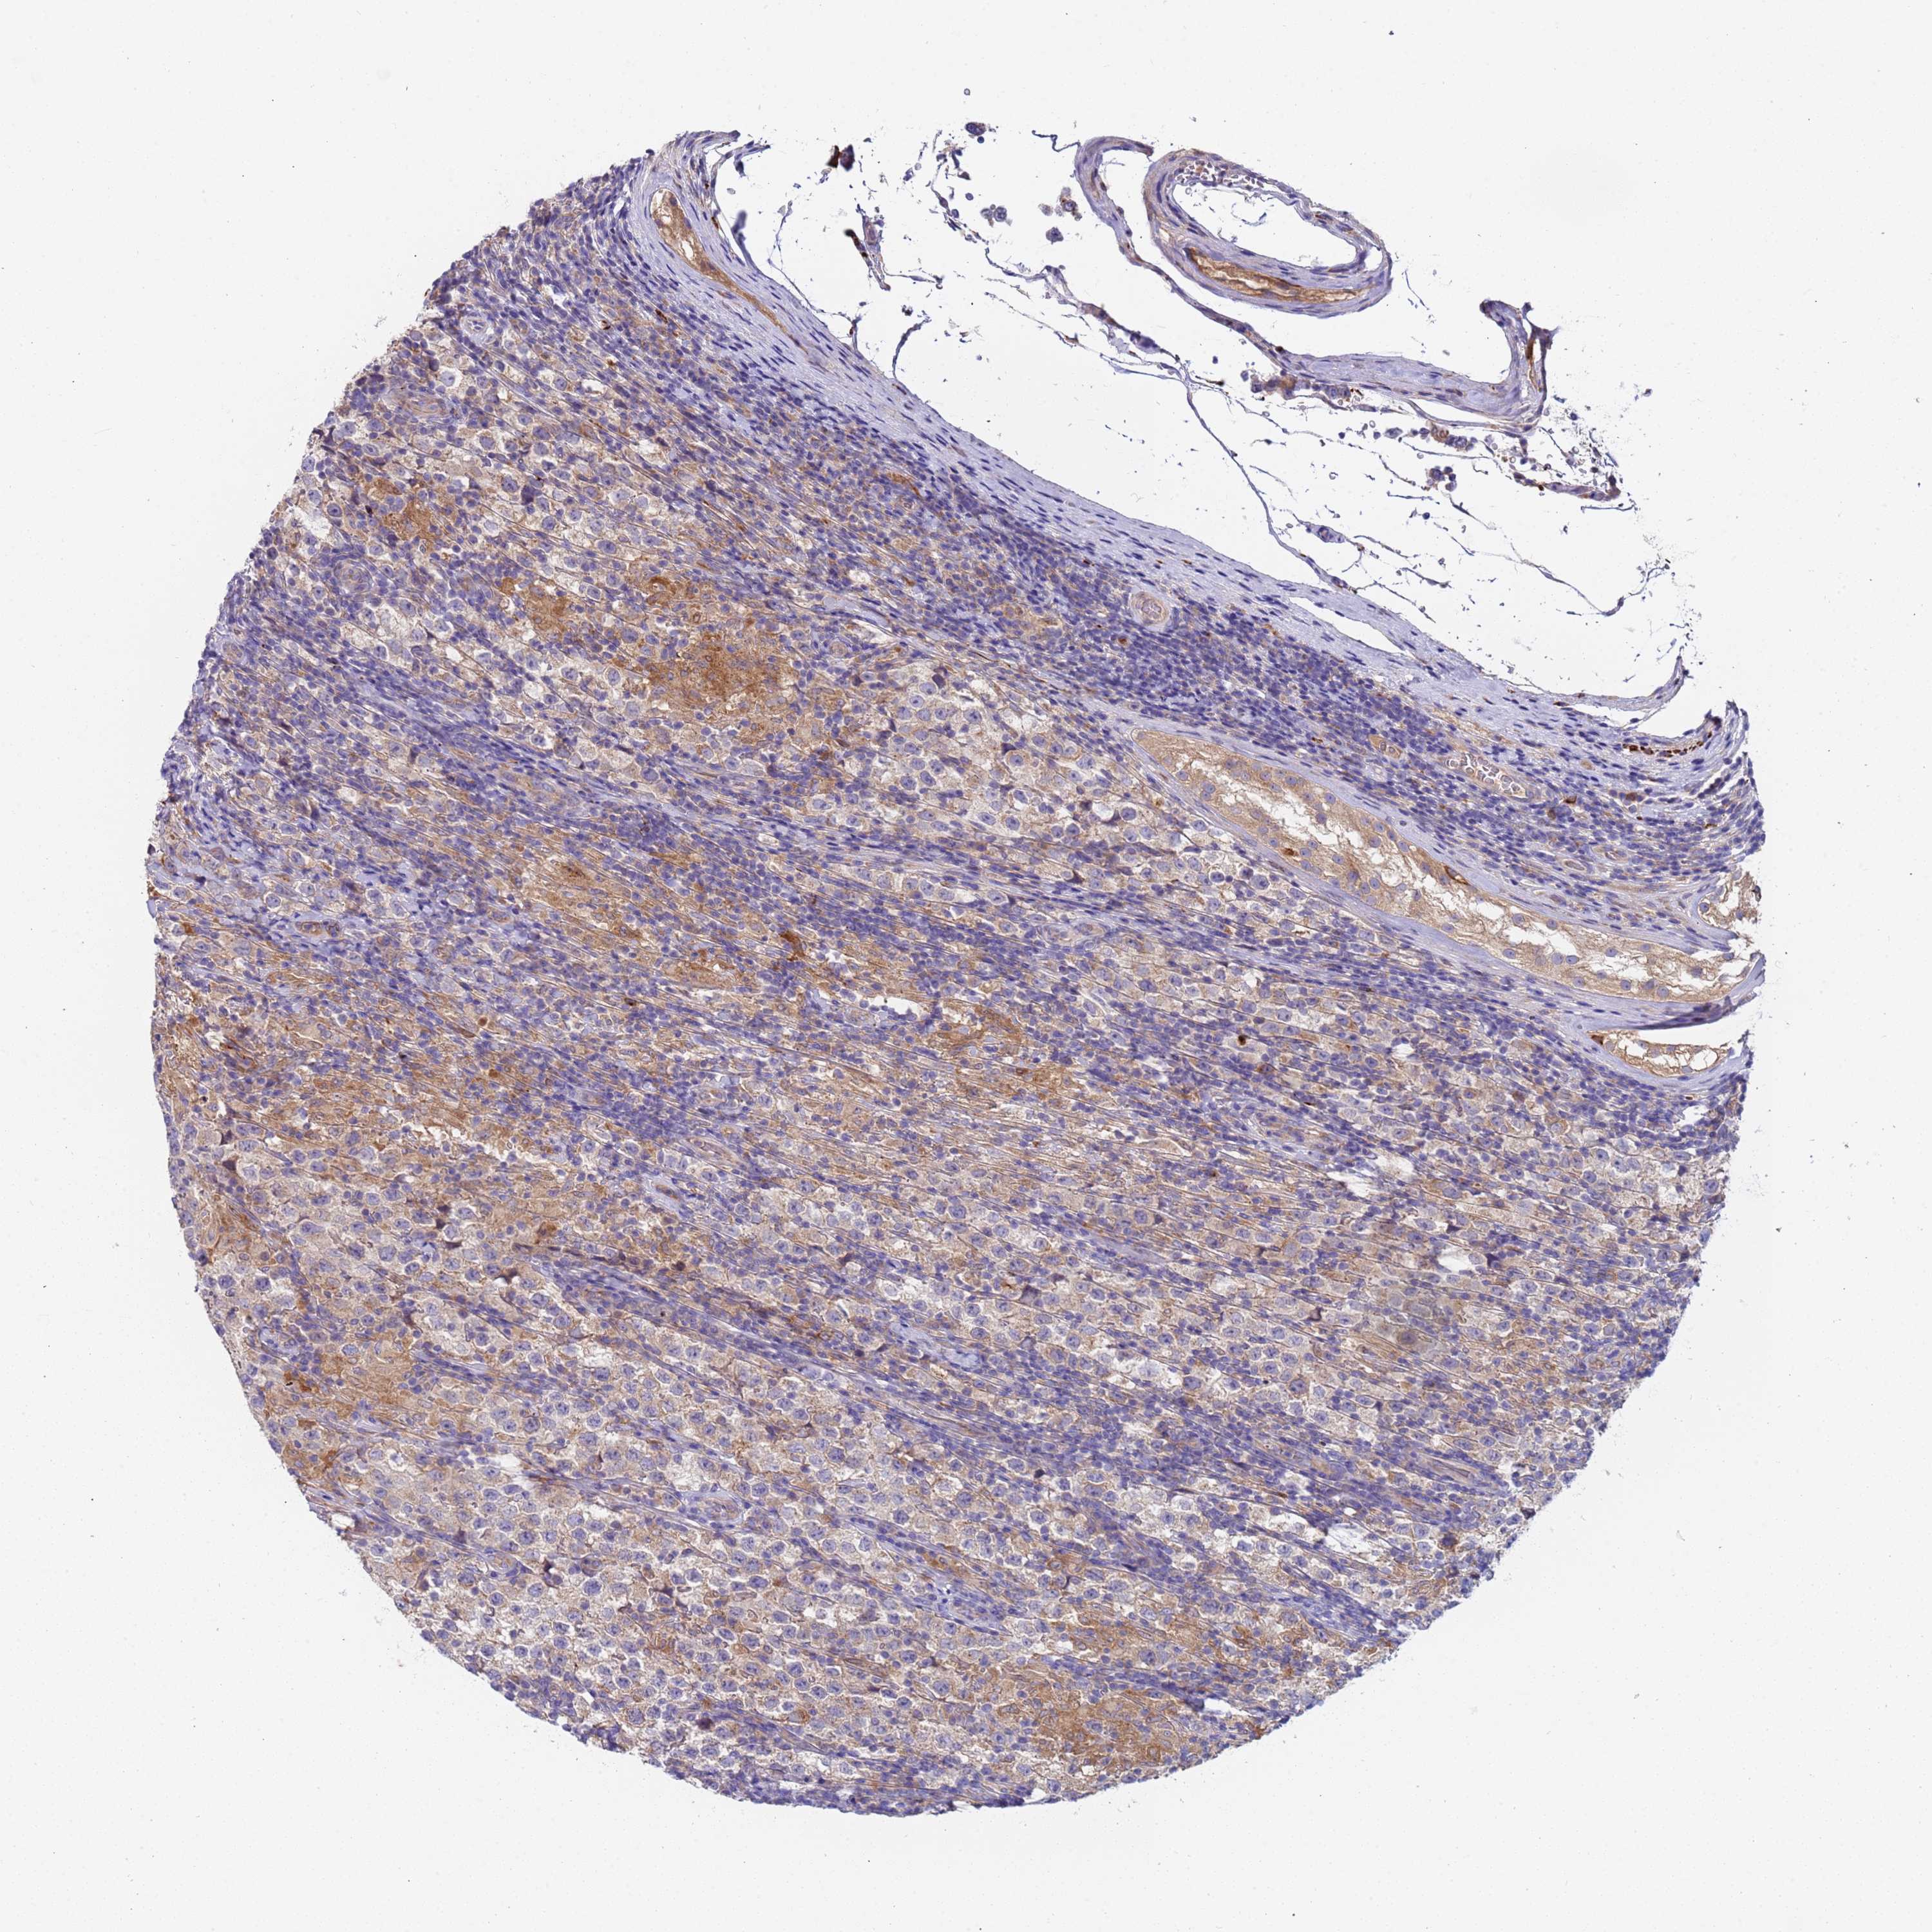

TESTIS CANCER - Protein expressioni

A mouse-over function shows sample information and annotation data. Click on an image to view it in a full screen mode. Samples can be filtered based on level of antibody staining by selecting one or several of the following categories: high, medium, low and not detected. The assay and annotation is described here.

Note that samples used for immunohistochemistry by the Human Protein Atlas do not correspond to samples in the TCGA dataset.

Antibody stainingi

Antibody staining in the annotated cell types in the current human tissue is reported as not detected, low, medium, or high, based on conventional immunohistochemistry profiling in selected tissues. This score is based on the combination of the staining intensity and fraction of stained cells.

Each image is clickable and will lead to virtual microscopy that enables deeper exploration of all samples and also displays staining intensity scores, fraction scores and subcellular localization as well as patient and tissue information for each sample.

Antibody HPA046936

Staining

High

Medium

Low

Not detected

Intensity

Strong

Moderate

Weak

Negative

Quantity

>75%

75%-25%

<25%

None

Location

Nuclear

Cytoplasmic/membranous

Cytoplasmic/membranous,nuclear

Carcinoma, Embryonal, NOS

Seminoma, NOS